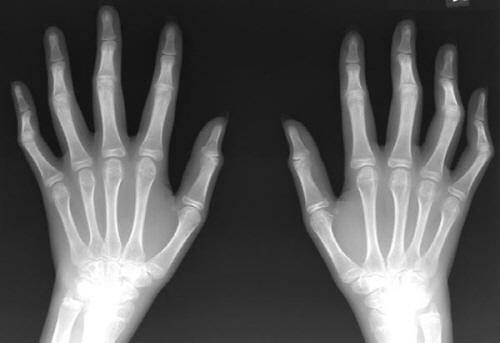

류머티즘 관절염은 신체 여러 부위에서 염증을 일으키는 만성 자가면역 질환이며 염증성 질환이다. 골관절염에 이어서 만성 관절염 중에서도 가장 흔한 원인의 질환이기도 하다. 류머티즘 관절염은 흔히 알고 있는 일반 관절염과는 다르다. 일반적으로 관절염이라고 하면 부상이나 노화 등으로 인해서 관절에 마모가 생기는 골관절염이다. 그리고 퇴행성 관절염은 일 할 때 손가락 마디가 붓고 아픈 증상이 심하다. 손가락 끝마디나 또는 중간 마디가 딱딱하게 돌출되었으면 퇴행성 관절염의 확률이 높다. 주로 50대 이상의 충장년층 여성에게서 많이 관찰되고 있다. 반복적인 수작업이나 노화로 인해서 연골이 닮아서 없어지고 대신에 뼈가 자라나는 현상이다. 반면에 류머티즘 관절염은 세균의 침투를 방어하다 면역계통에 이상이 생기는 것이다. 그래서 세포의 염증을 물질이 과다 분비되면서 신체 전신에 관절염을 일으키는 질환이다. 주로 손 관절에서 시작하지만 무릎이나 어깨와 발목 등 전신 관절에 나타나는 경우가 많다. 염증 물질이 가장 활발하게 움직이는 시간은 새벽 3시 정도 된다. 그래서 아침에 일어나면 경직감이나 뻣뻣한 증상이 발생하는 조조강직이 주요 증상으로 나타난다. 아침에 활동을 시작하면 증상은 서서히 완화되고 오후에는 호전이 되는 양상을 보인다. 류머티즘 관절염의 원인은 정확하게 밝혀져 있지는 않지만 유전적인 요인과 흡연 등 환경적인 요인이 영향을 주는 것으로 전해진다.

류머티즘 관절염은 조기 발견과 조기 치료가 매우 중요하다. 이유는 완치가 힘든 질병이기 때문이다. 치료의 목적은 염증을 조절하여 통증을 해소시키고 관절의 손상을 늦추며 기능을 최대한 보존하는 데 있다고 한다. 치료하는 방법은 비약물치료와 약물치료가 있다. 비약물치료는 관절에 급성염증이 있을 때 휴식과 안정을 취해야 한다. 그러나 오랫동안 누워서 휴식을 취하게 되면 관절이 뻣뻣해지므로 잠깐씩 자주 쉬는 게 좋다. 그리고 염증이 없는 관절에 대해서는 가벼운 운동이나 스트레칭을 해주는 것이 좋다. 염증이 가라앉을 때는 운동을 시작해야 한다. 류머티즘관절 환자는 관절운동을 하지 않으면 몸이 더욱 경직된다. 관절이 움직일 수 있는 범위를 최대한 굽혔다 폈다 하는 운동을 3회 정도 실시하는 것이 중요하다. 추천되는 운동으로는 체조, 스트레칭, 가볍게 걷기, 수영, 자전거 정도가 있다. 그리고 축구, 농구, 테니스, 등산 등 관절에 무리를 주는 운동은 피해야 한다. 약물치료에는 비스테로이드성 항염제와 항류머티즘제 등이 있다. 비스테로이드성 항염제는 통증과 염증을 가라앉히기 위해 사용된다. 그러나 질병의 진행자체를 막을 수는 없다. 항류머티즘은 면역역제제의 일종으로 관절염을 유발하고 악화시키는 신체의 면역기능을 억제하고 조절하는 효과가 있다.